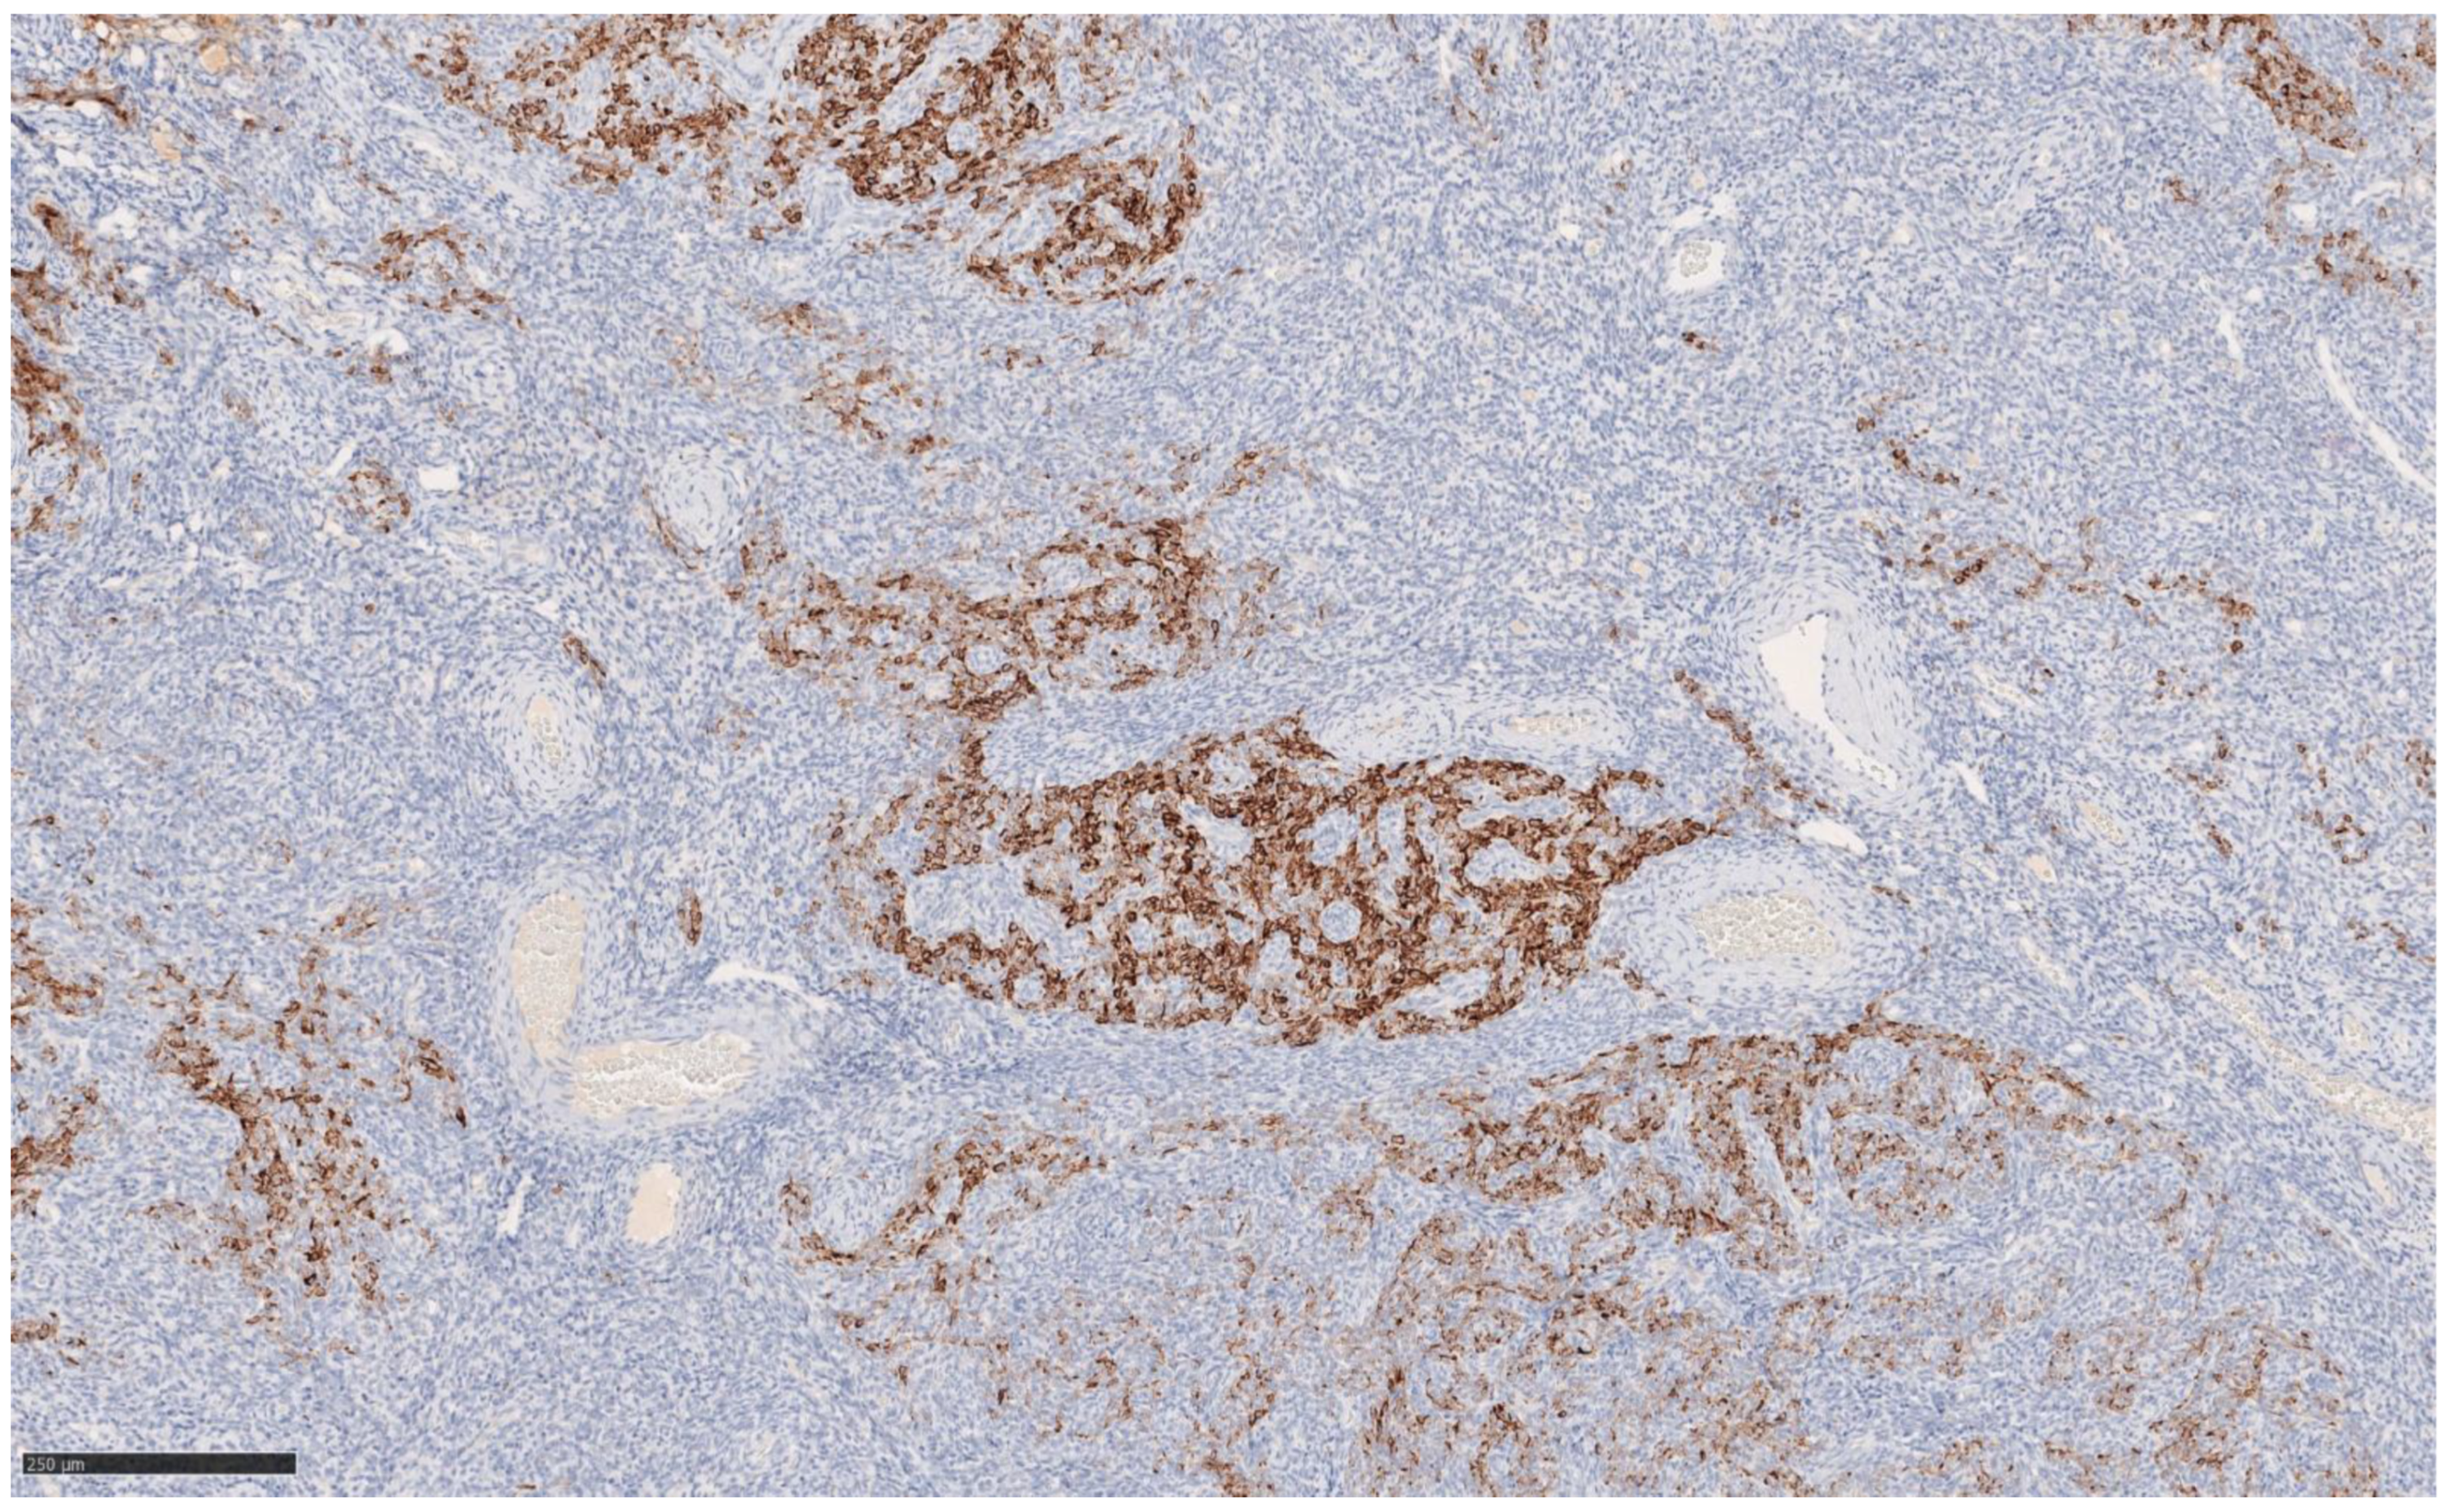

4.3. Histological and Immunohistochemical Features